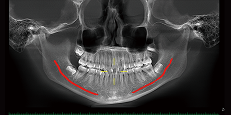

Implant Simulation

Neural tubes will be highlighted, which presents a relationship between the location of the implant and optimal length. This is the best way to improve the success rate for implant surgery.

Neural Tube Automatic Labeling

Label the neural tube automatically in the CT image, providing great convenience for diagnosis.